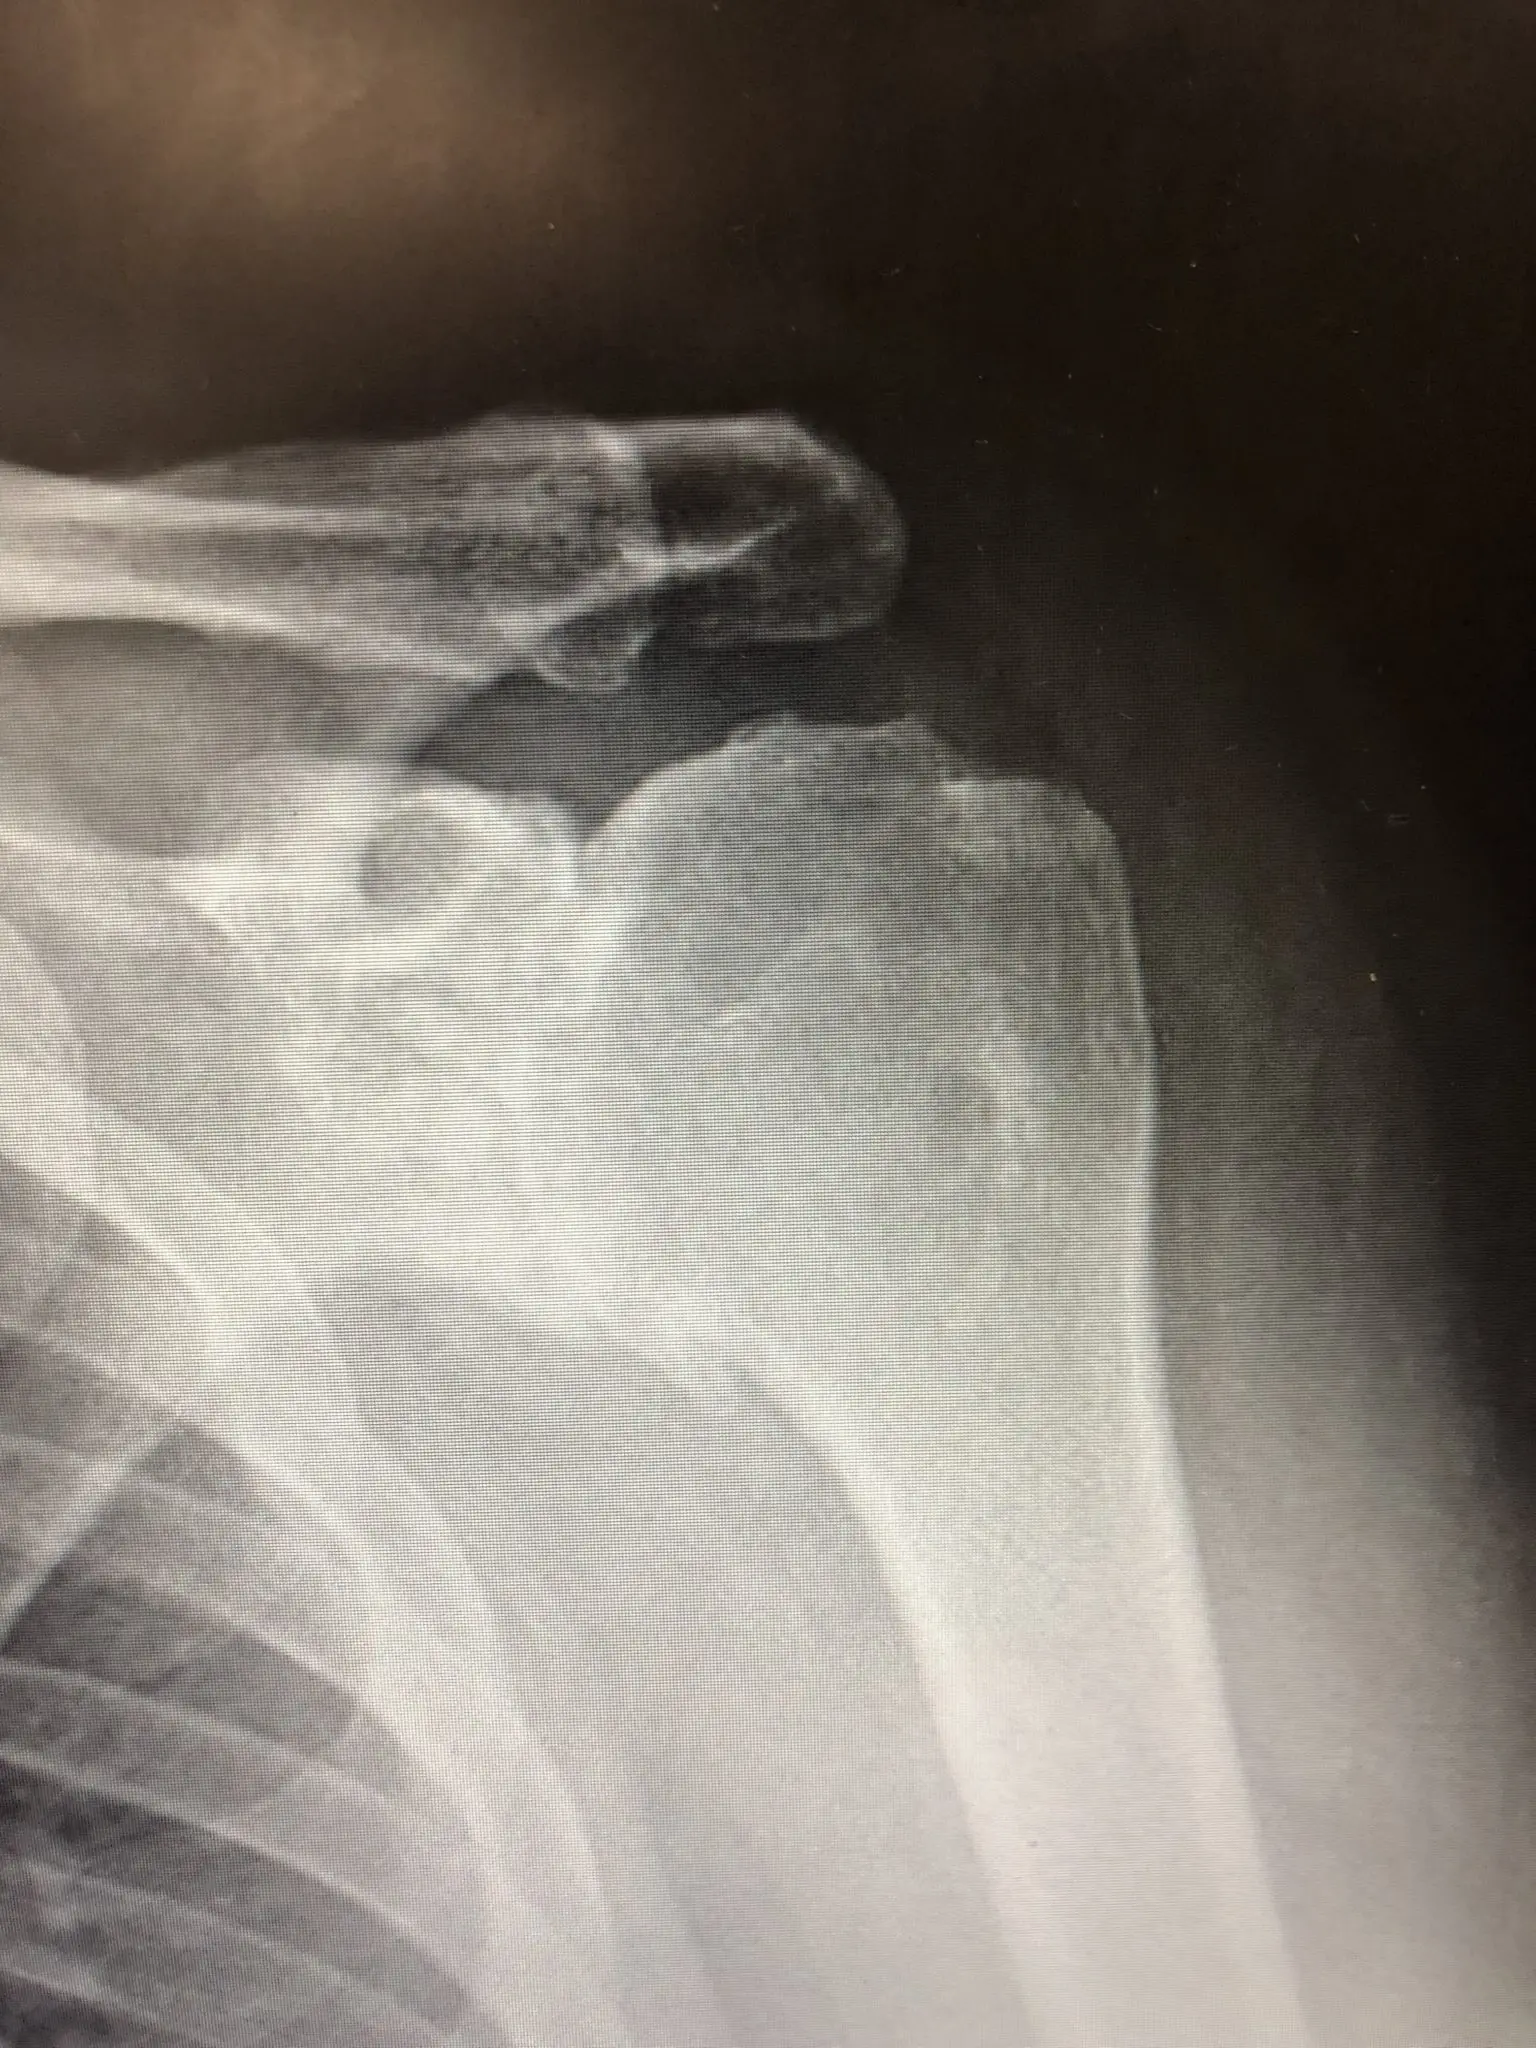

Zdjęcie RTG - choroba zwyrodnieniowa barku

Choroba zwyrodnieniowa stawów barku

Choroba zwyrodnieniowa stawów (artroza) jest najczęściej występującym schorzeniem układu ruchu6. Polega na niszczeniu chrząstki kości tworzących staw. U osób po 50. roku życia zmiany zwyrodnieniowe związane są zazwyczaj ze zużyciem powierzchni stawowej. Ryzyko rozwoju choroby jest większe, jeśli bark był nadmiernie obciążany (np. u pracowników fizycznych), a także jeśli wcześniej występowały urazy.

W przypadku średniozaawansowanych zmian zwyrodnieniowych stosowana bywa metoda małoinwazyjna (artroskopowa): wprowadzenie do stawu kamery i urządzeń chirurgicznych w celu uwolnienia przykurczów torebki stawowej i usunięcia wyrośli kostnych, które ograniczają ruch.

Mimo, że tą operacją nie odtwarzamy powierzchni stawowej, jesteśmy w stanie – szczególnie u osób bardzo aktywnych i w wieku poniżej 60. roku życia – poprawić zakres ruchu i przywrócić je do normalnego funkcjonowania – dodaje dr Kowalski.